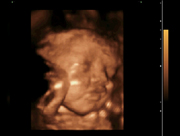

Fetal,4D

29 Weeks Fetal Face, 4D Mode